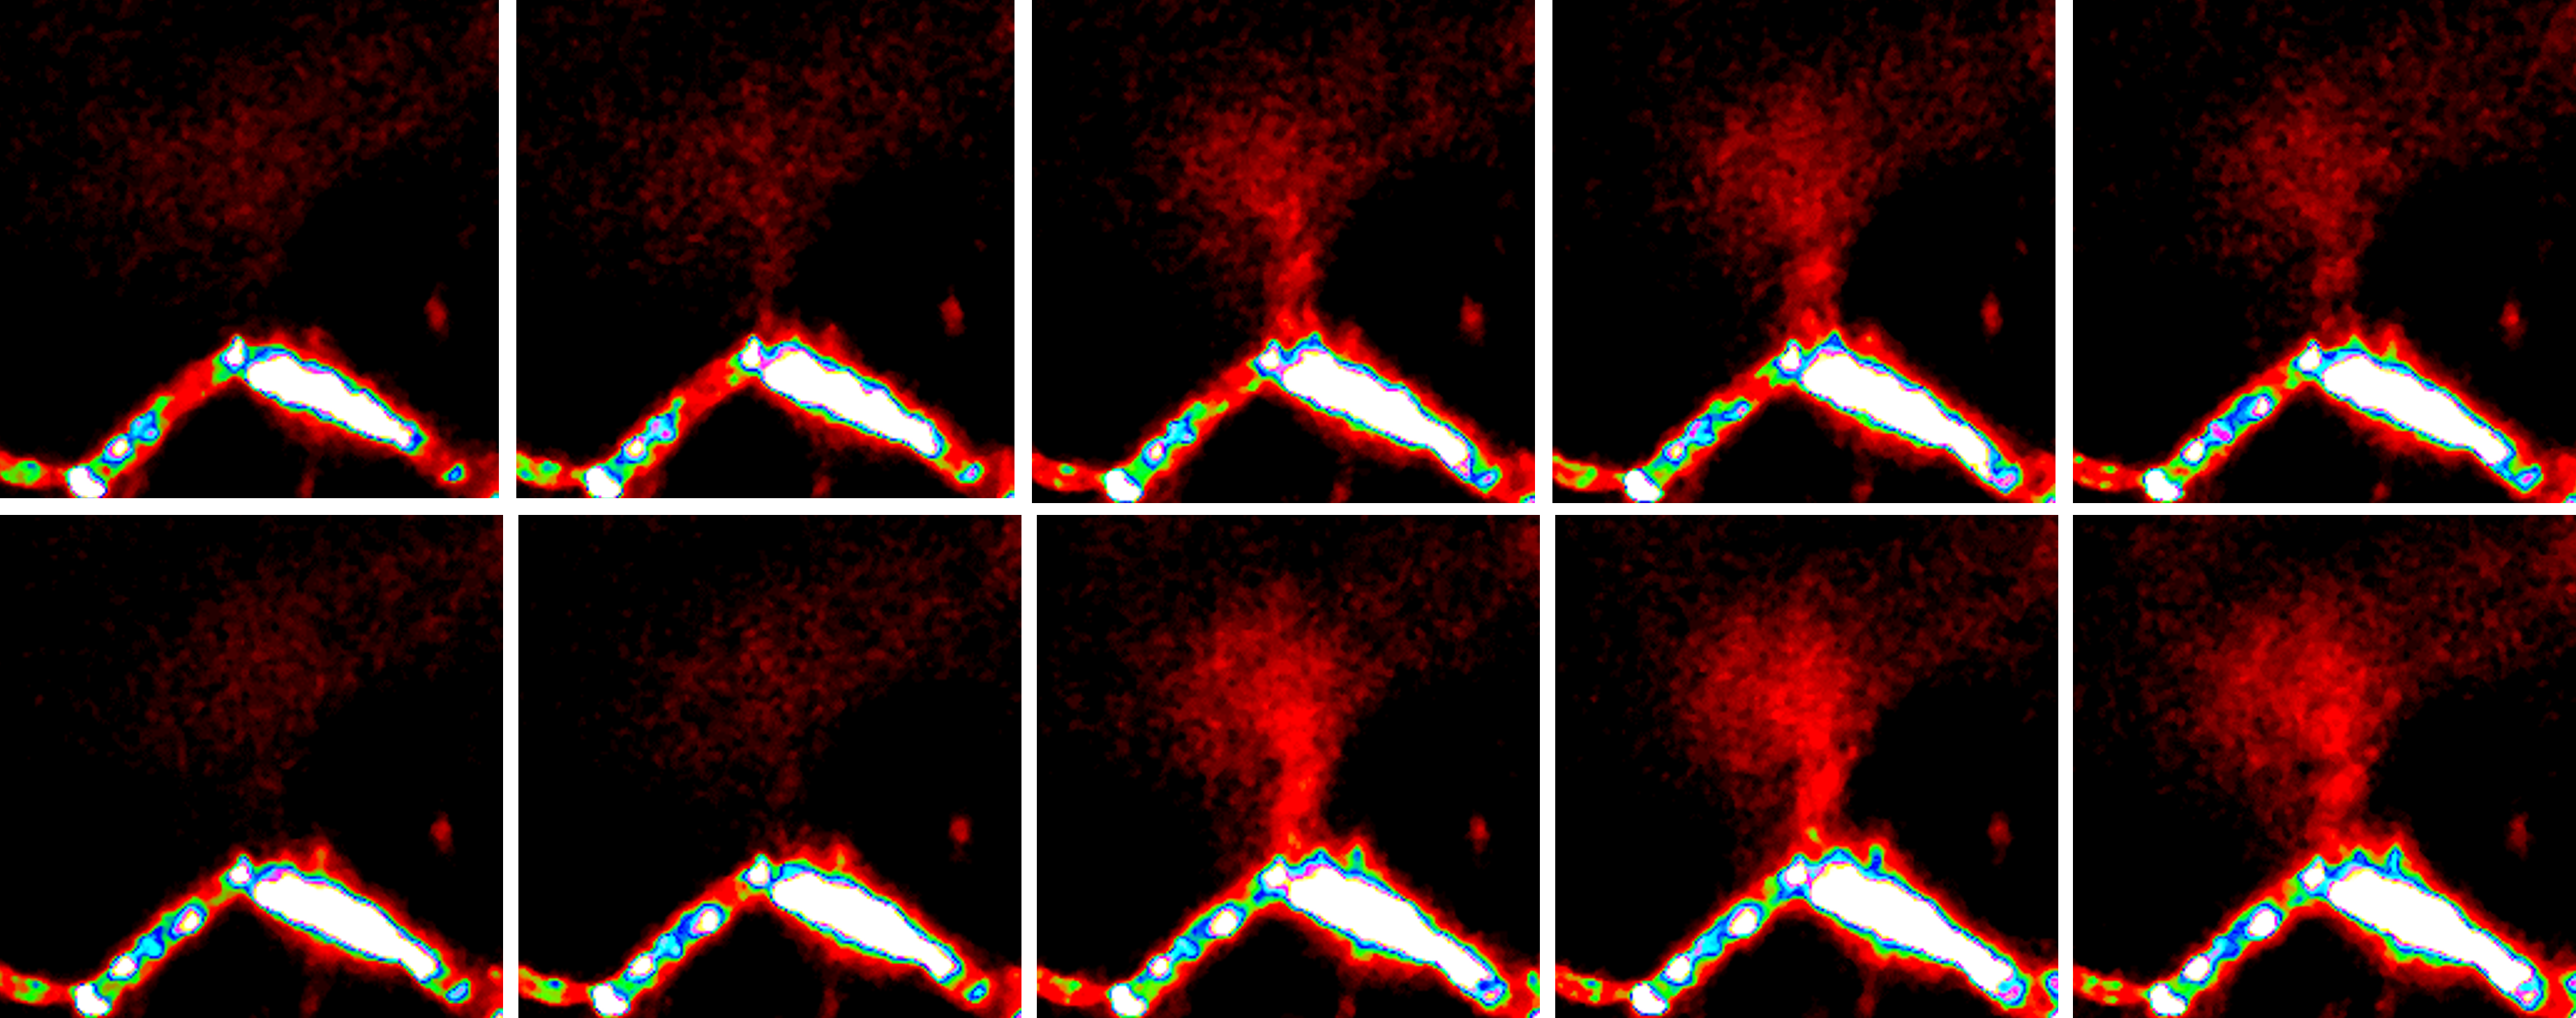

2. In Vivo Fate of Drug Delivery Systems

We systematically investigate the in vivo behavior and fate of drug delivery systems using advanced imaging and analytical tools, including intravital fluorescence microscopy, transmission electron microscopy, and synchrotron radiation-based imaging. Our studies focus on how delivery systems interact with physiological and immune barriers, such as the mononuclear phagocyte system (especially in the liver and spleen), vascular endothelium, and immune cell subsets. We analyze circulation kinetics, biodistribution profiles, cellular uptake mechanisms, and clearance pathways to elucidate the principles that govern delivery efficiency and target-site accumulation. These mechanistic insights guide the rational optimization of carrier design to improve therapeutic precision and minimize systemic toxicity.

2025[1] W. Jiang#, Z. Guo#, Q. Wang#,*, Z. Chen, W. Dong, Q. Liang, Y. Hao, H. Pan, C. Zeng, H. Liu* ,Y. C. Wang*. Enhanced nanoparticle delivery across vascular basement membranes of tumours using nitric oxide. Nature Biomedical Engineering. 2025, doi:10.103

2024[1] Q. Wang#, Q. R Liang#, J. X. Dou, H. Zhou, C. C. Zeng, H. M. Pan, Y. Q. Shen, Q. Li, Y. Liu, D. T. Leong*, W. Jiang*, Y. C. Wang*. Breaking through the basement membrane barrier to improve nanotherapeutic delivery to tumors. Nature Nanotechnology. 202